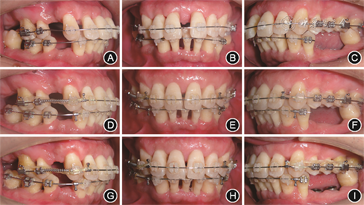

(3)正畸治疗:上前牙牙周再生性手术后10周转正畸科治疗,正畸过程中每月定期检查口腔卫生并酌情进行牙周治疗。正畸治疗14个月下前牙压低基本完成,牙周再评估时31、32已形成骨下袋,建议行牙周再生性手术;牙列基本排齐,缺牙区间隙

龈距离及近远中距离基本充足,建议合理安排种植修复时机(图8)。

像;B:治疗后4个月正面

像;C:治疗后4个月左侧

像;D:治疗后14个月右侧

像;E:治疗后14个月正面

像;F:治疗后14个月左侧

像;G:治疗后20个月右侧

像;H:治疗后20个月正面

像;I:治疗后20个月左侧

像